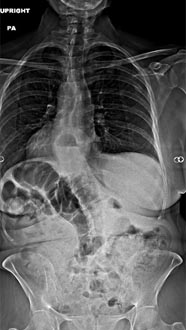

35 year old man presenting with severe neck pain with radiation down the right arm with right bicep weakness. MRI with large right C5-6 disc extrusion.

Postoperative xrays after C5-6 anterior cervical disc replacement. Complete resolution of arm pain and full painless range of motion of his neck.